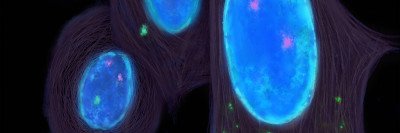

In addition, I conduct research into how cancer can change its genetic makeup to evade treatments and spread to distant organs. One genetic error that has been linked to cancer aggressiveness and resistance to treatment is called chromosomal instability (CIN). My lab is dedicated to learning about CIN and using this information for therapies that tackle aggressive cancers and their ability to spread.